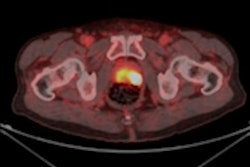

To shed more light on the topic, the researchers retrospectively looked at 388 patients with confirmed prostate cancer, all of whom underwent whole-body Ga-68 PSMA-11 PET/CT scans (Biograph 64 TruePoint or 2010 Biograph mCT 64, Siemens Healthineers) for primary staging, biochemical recurrence, or restaging from September 2017 to May 2018. Subjects received a median of 196.1 MBq (5.3 mCi) of Ga-68 PSMA-11, with a median tracer uptake period of 60 minutes.

The images detected bone metastases in 12 (13%) of 93 patients who underwent initial staging; 44 (20%) of 225 patients with biochemical recurrence; and 49 (70%) of 70 restaging patients. As expected, the incidence of bone metastases increased concurrently with rising serum PSA levels.

"Surprisingly, 38 of 216 patients (17.6%) with serum PSA levels of less than 5.0 ng/mL were found to have PSMA-positive lesions suspicious for bone metastases," the authors wrote.